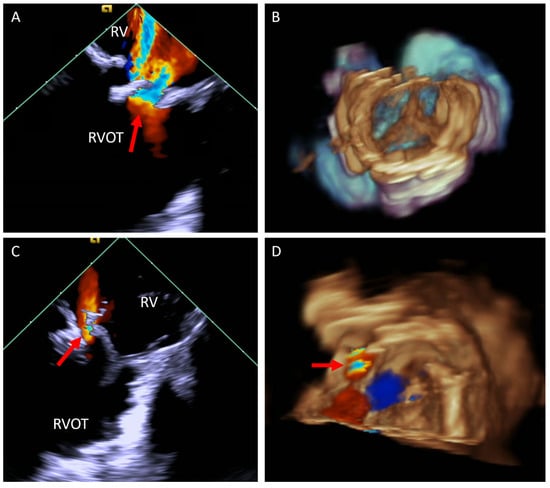

5.3. Transcatheter Pulmonary Valve Replacement (TCPVR)